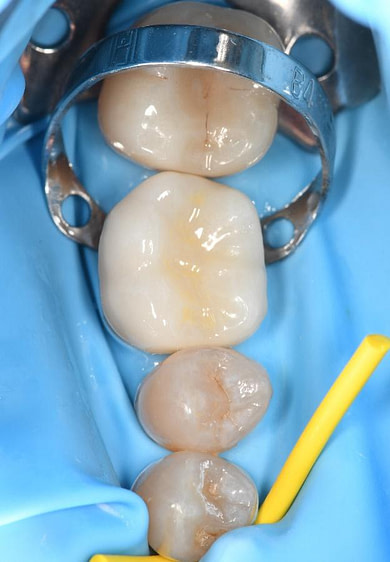

Following the successful surgical placement of the implant, the focus shifted to the restorative phase of the treatment.

Three months after the implant surgery, a thorough post-operative assessment revealed excellent healing and implant stability.

Digital impressions were captured using the TRIOS 4 intraoral scanner, and the implant-supported crown was designed using 3Shape Design Studio.

The crown was milled from a high-strength, multilayered zirconia and hand-finished to achieve a lifelike appearance.

At the final appointment, the crown was securely attached to the implant, resulting in a beautiful, natural-looking restoration.

Implant detection matches the scan body in the intraoral scan with the digital library. A colour scale is given to show the accuracy of the matching (Green is good).